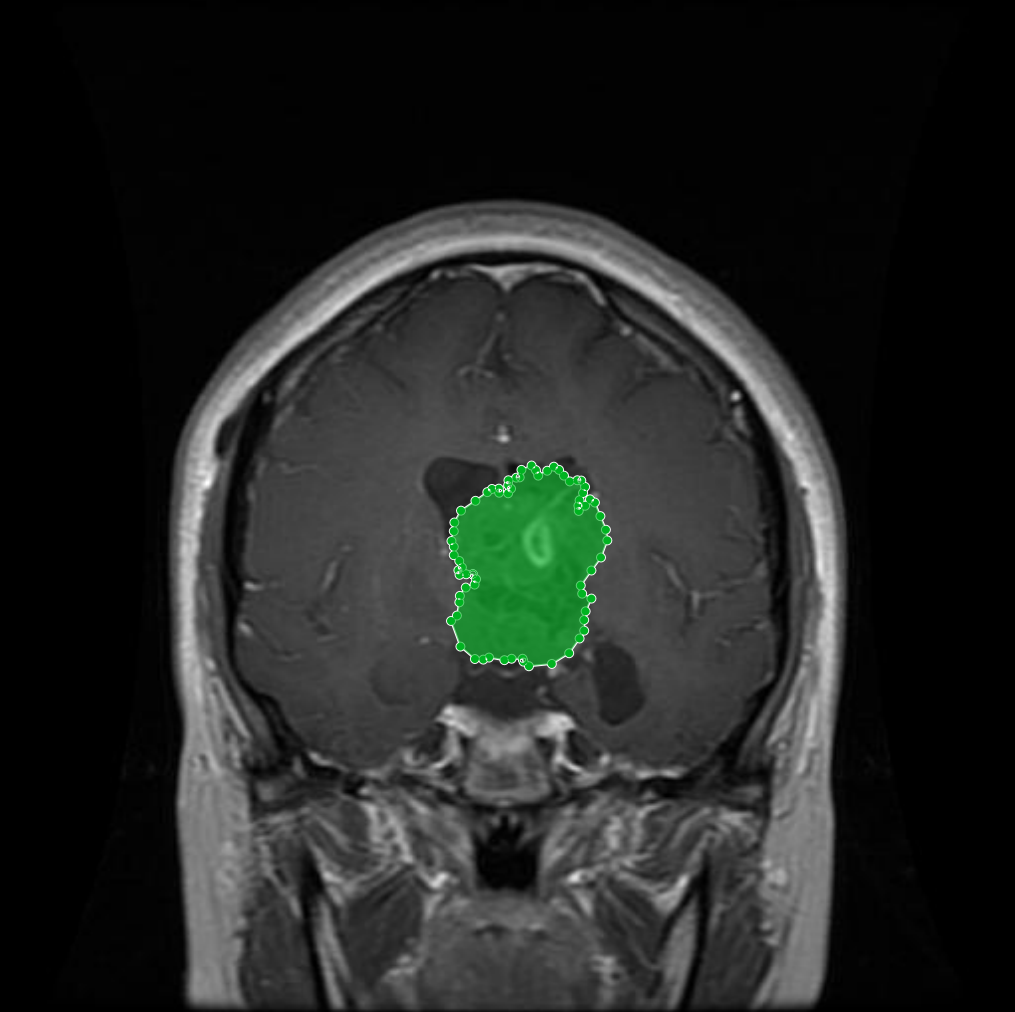

Meningioma: Meningiomas arise from the meninges and are generally well‑circumscribed and homogeneous, making them easier to segment. However, their location adjacent to critical structures such as dural sinuses and cranial nerves can complicate diagnostic tasks. An example of a meningioma and its segmentation mask is presented in Figure 2, illustrating the clarity of its boundaries.

Figure 2: Samples of Meningioma segmentation across different imaging planes

The dataset encompasses four distinct classes: ”Glioma”, ”Meningioma”, ”Pituitary” tumors, and ”non-tumorous”. As detailed in Section Overview of Brain Tumors, each class presents unique characteristics and complexities. This subsection offers representative visual examples from each class, including raw MRI scans alongside their annotated tumor masks, emphasizing the diversity and precision of the dataset. Glioma: Gliomas are irregularly shaped and often infiltrate surrounding tissues, presenting significant challenges for precise boundary definition. These complexities require robust segmentation techniques to capture their variable morphology. As shown in Figure 1, gliomas exhibit irregular and diffuse growth patterns, which are highlighted through annotated tumor masks. Meningioma: Meningiomas arise from the meninges and are generally well‑circumscribed and homogeneous, making them easier to segment. However, their location adjacent to critical structures such as dural sinuses and cranial nerves can complicate diagnostic tasks. An example of a meningioma and its segmentation mask is presented in Figure 2, illustrating the clarity of its boundaries. Pituitary Tumors: Located at the base of the brain near critical structures like the optic chiasm, pituitary tumors demand careful delineation to avoid diagnostic errors. As shown in Figure 3, the segmentation accurately captures the tumor’s boundaries without encroaching on adjacent critical regions. Non-tumorous: This control class includes both healthy brain scans without visible abnormalities and scans with non-neoplastic, space-occupying lesions (e.g., cysts, abscesses, or vascular malformations). Incorporating such cases improves the dataset’s robustness for both binary (tumorous vs. non-tumorous) and multi-class classification tasks. Figure 4 presents representative examples of healthy and non-tumorous lesion cases across different imaging planes.Tumor Mask and Annotation Quality